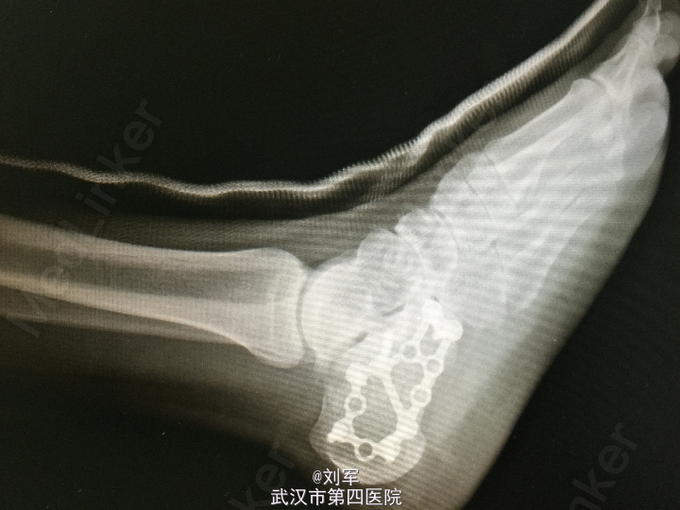

左足跟肿胀,瘀斑,局部压痛及叩痛。左踝活动受限。足趾血运可,感觉存在。左跟骨CT平扫+三维重建:跟骨粉碎性骨折。

左跟骨粉碎性骨折。 入院后完善检查,入院后第六天行开放复位内固定术。

跟骨骨折为创伤骨折常见病,多因高处坠下,足跟着地致伤。根据跟骨CT平扫+三维重建检查,决定治疗方案。